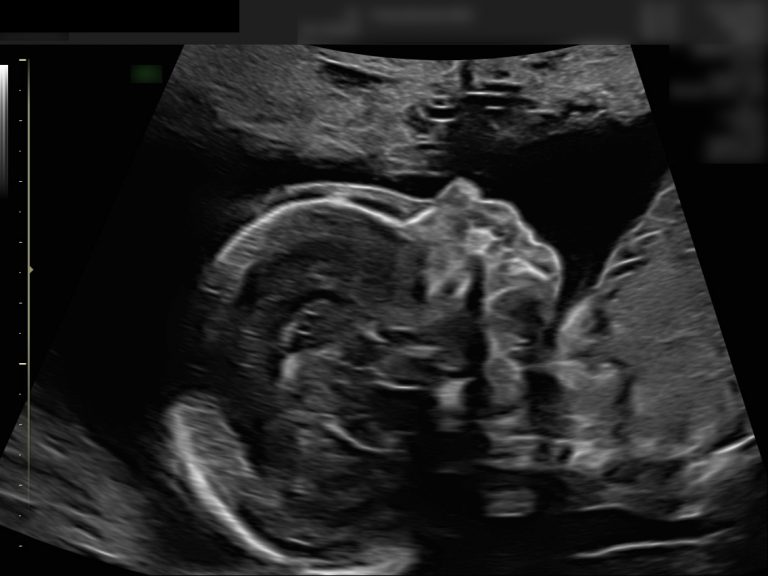

Eine detaillierte Ultraschalluntersuchung kann hier helfen, die Entwicklungsschritte sichtbar zu machen und Risiken rechtzeitig zu erkennen.

Das Ersttrimesterscreening ist die erste umfassende Untersuchung des gesamten Kindes. Es ermöglicht, viele Fehlbildungen und Entwicklungsstörungen frühzeitig auszuschließen und wichtige Erkenntnisse über die Gesundheit von Mutter und Kind zu gewinnen.